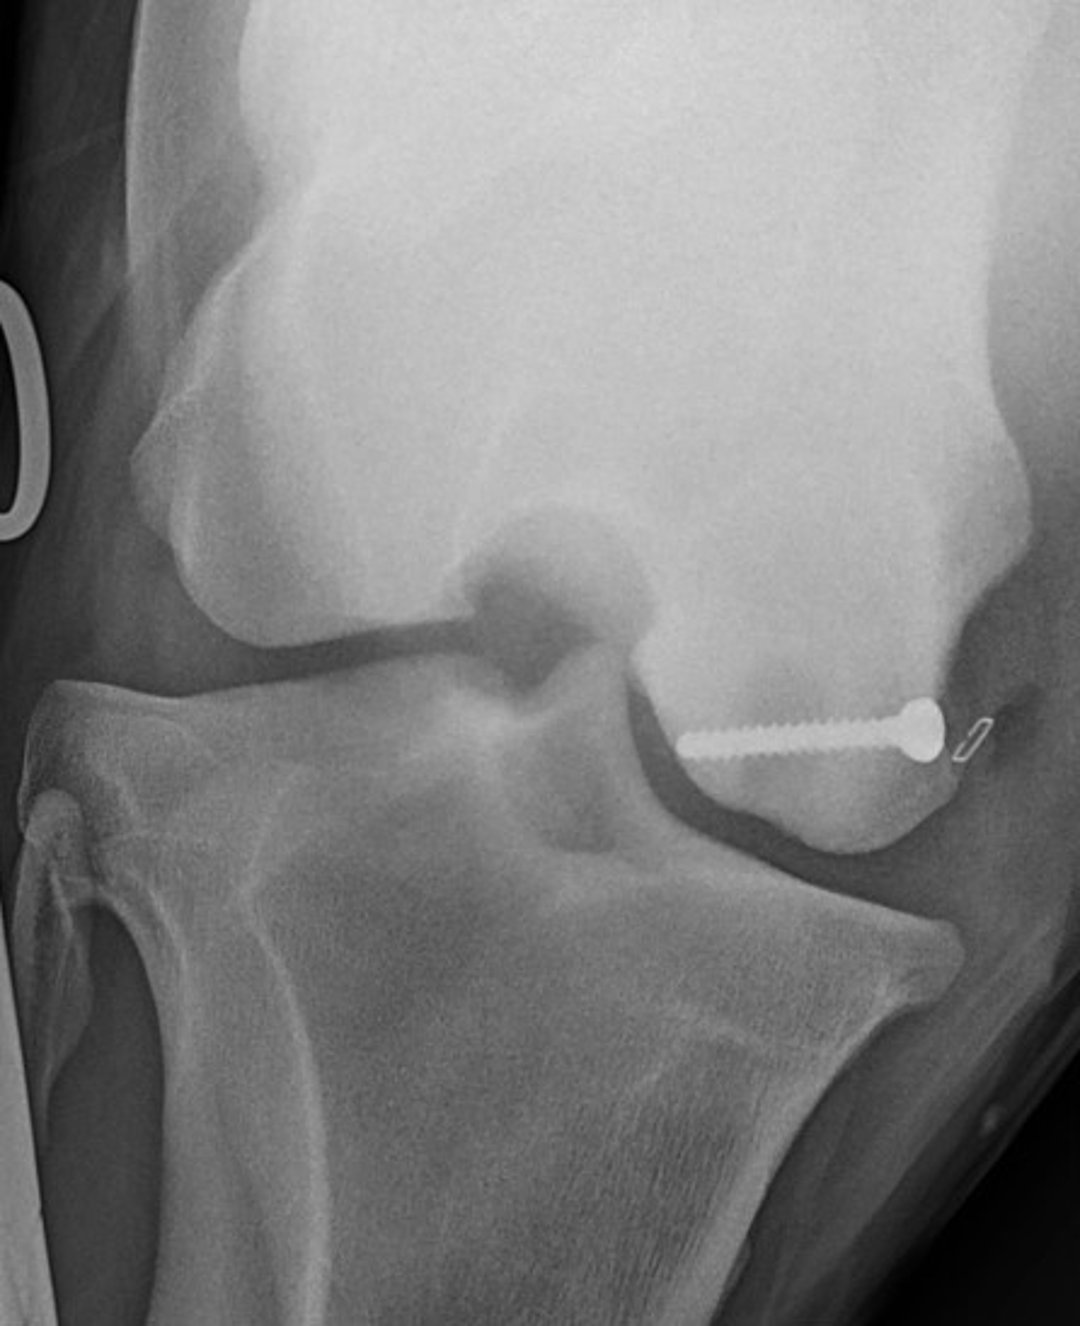

Transcondylar lag screw placement, radiograph, horse

Intraoperative radiograph of a horse, demonstrating transcondylar lag screw placement. The skin staple denotes marking at the skin before lag screw placement.

Courtesy of Dr. Sushmitha Durgam.